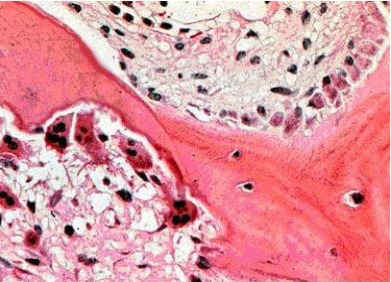

【染色原理】細胞中的堿性磷酸酶,在堿性緩沖液中,催化底物水解,生成物進而與一種穩定的重氮鹽偶聯,生成不溶性的偶氮染料,沉著于有CAKP活性的部位。染色結果為血涂片中細胞核呈紫藍色(蘇木素復染)或綠色(甲基綠復染),陽性者胞漿中出現紅至紅棕色顆粒,有些為棕褐色或咖啡色顆粒。